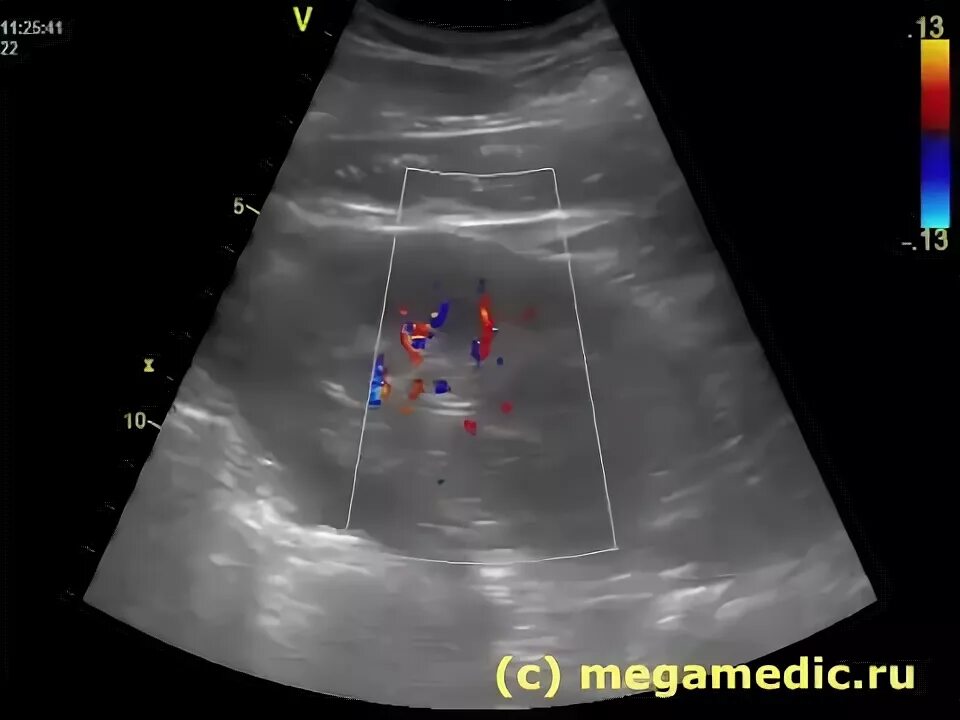

Диффузные изменения почек